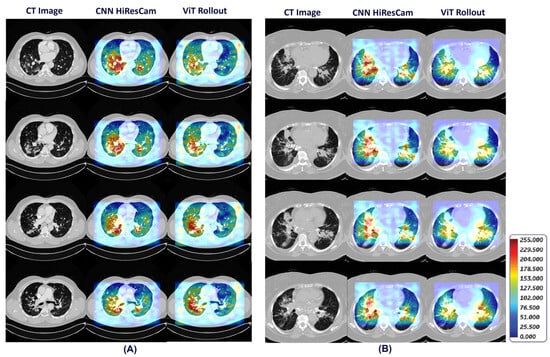

- Our framework also provides visual explainability for the classification of pulmonary sarcoidosis vs. lung malignancies (LCa) that suggests regions of interest that are considered important by the network for making the prediction.

2.3. Generating Visual Explanations for Predictions

- Draelos, R.L.; Carin, L. Hirescam: Faithful location representation in visual attention for explainable 3d medical image classification. arXiv 2020, arXiv:2011.08891. [Google Scholar]

- Abnar, S.; Zuidema, W. Quantifying attention flow in transformers. arXiv 2020, arXiv:2005.00928. [Google Scholar]